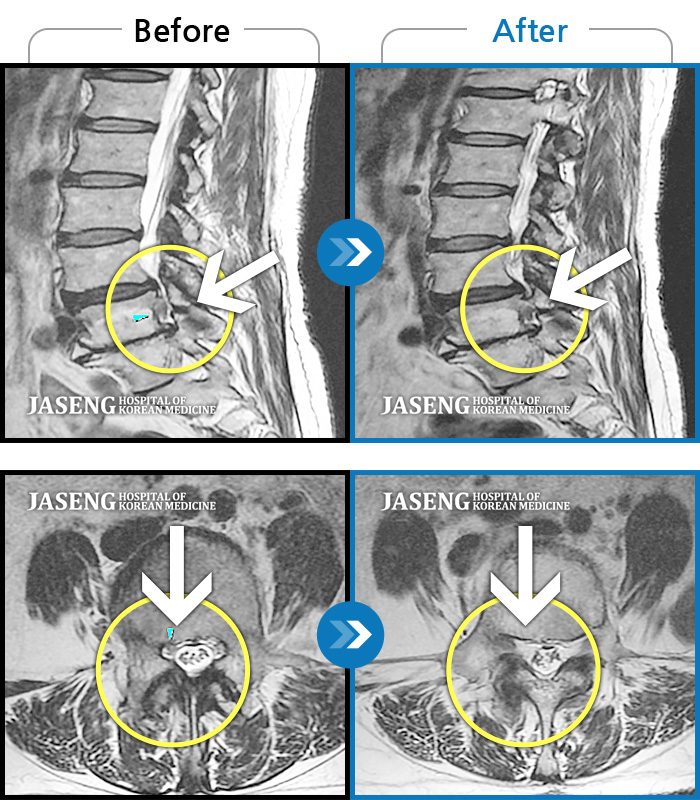

허리디스크

보라매 · 왕오호 원장

좌측 허리 통증 및 좌측 다리 저림

촬영시기

2016.05.21 ~ 2018.04.13

2018.12.28

조회수 692